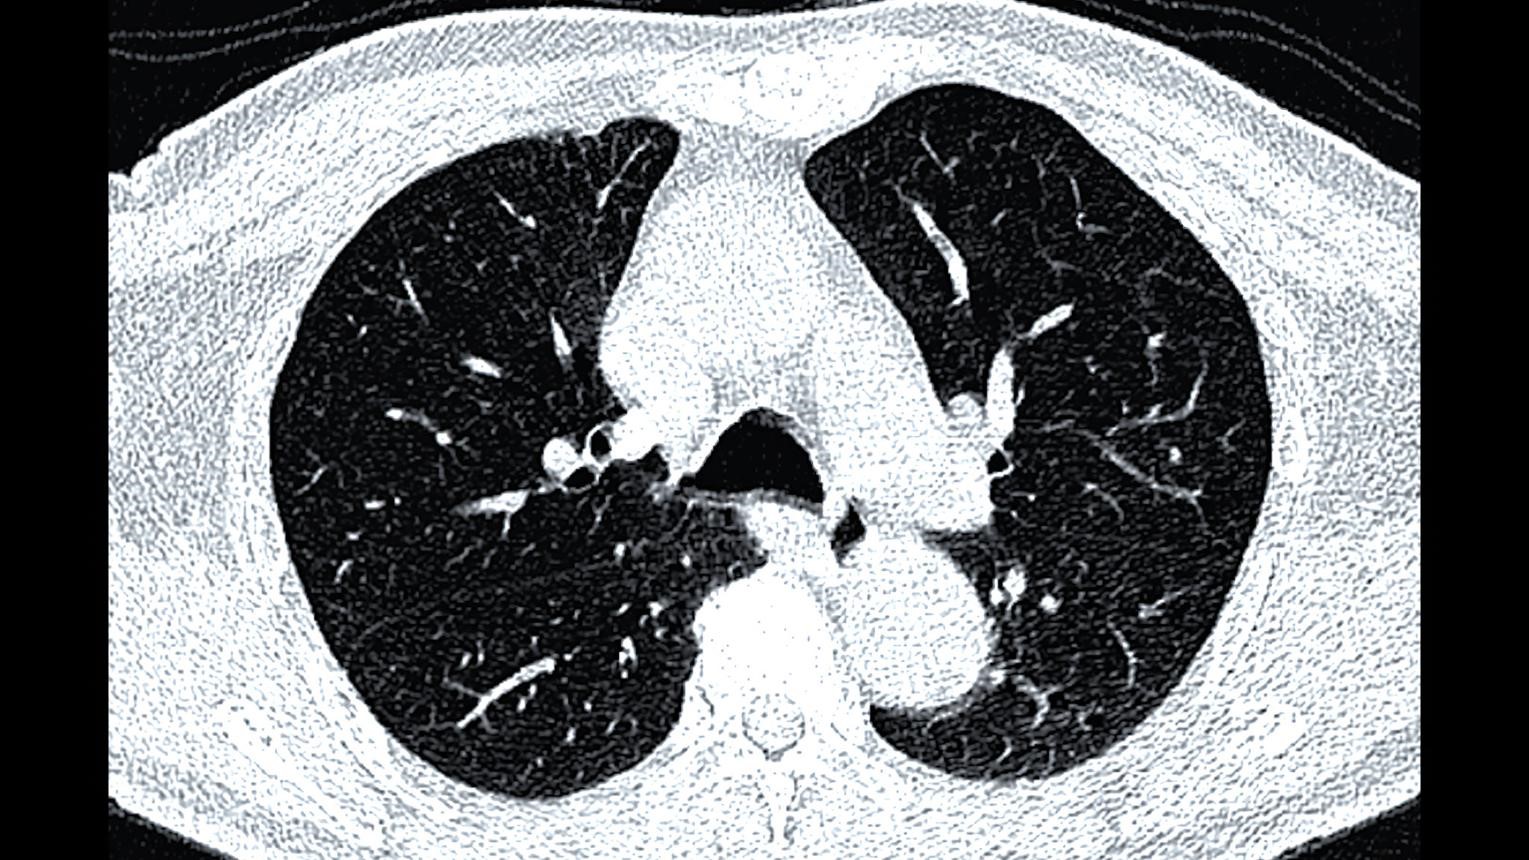

CT torace Galați – Screening cancer pulmonar (low-dose)

Diagnostic precoce. Fără durere. Fără contrast. Tehnologie modernă.

Screening pentru cancer pulmonar

Evaluare noduli pulmonari

Cauți CT în Galați? Alege varianta corectă: CT low-dose

Nu orice CT este potrivit pentru plămâni.

CT toracic low-dose este recomandarea standard europeană pentru:

• depistarea precoce a cancerului pulmonar

• monitorizarea nodulilor

• screening la pacienți cu risc